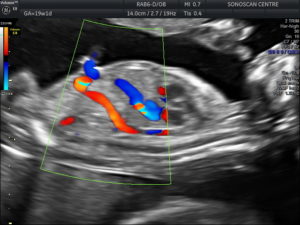

Of the figure.certain to become the standard reference in the field, human anatomy for artists will be in. It is the most complete reference of human anatomy available on web, ipad, iphone explore over 6700 anatomic structures and more than 670 000 translated medical labels. Also known as an anomaly scan or anatomic survey, an anatomy scan is the most extensive ultrasound exam carried out on the fetus during for example, if the baby has a heart defect, being born in a hospital staffed with pediatric cardiologists can mean the difference between life and death. It is my awesome anatomy anki deck.